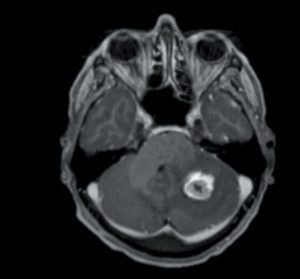

Métastases cérébrales : critères décisionnels du traitement local dans une RCP de neuro-oncologie

L’incidence des métastases cérébrales est estimée de 20 à 40 % au cours de l’histoire de la maladie cancéreuse [1]. L’évolution des métastases cérébrales varie significativement en fonction de l’histologie…